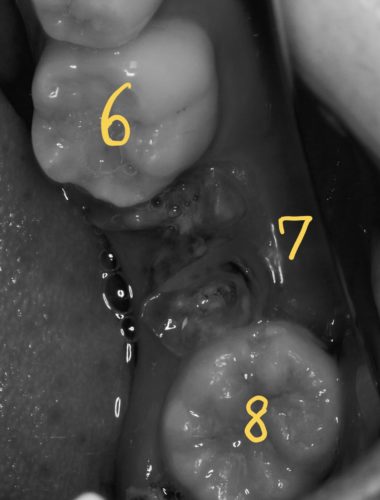

この方の『7』の歯のように、保存が難しい場合、抜いた後に欠損を補う方法として、

親知らずの移植、という処置があります